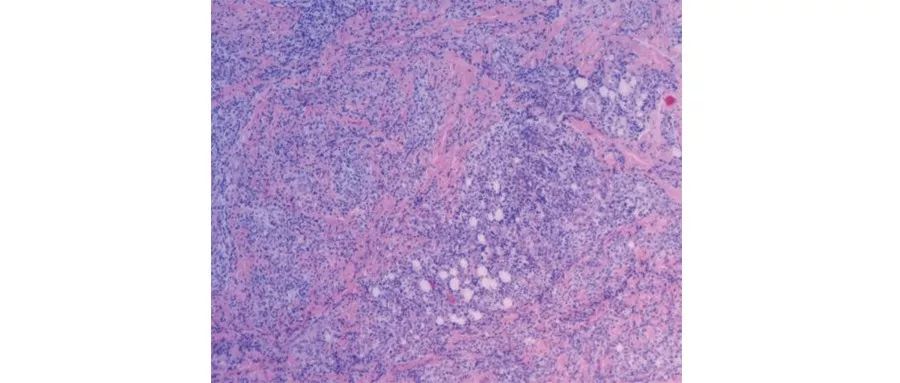

病理分析显示局部嗜酸细胞性聚集,肉芽肿性炎症(图)。

上部分为低倍镜观察,下部分为高倍镜所见。

诊断经过:本次入院以后,考虑到患儿克罗恩病起病年龄小、肺部真菌感染治疗效果不理想,并且有反复肛周脓肿及皮肤感染,怀疑存在原发性免疫缺陷病。对患儿及其父母、弟弟进行了白细胞吞噬氧化功能检测,呼吸爆发试验提示:患儿中性粒细胞活化率为0.027;患儿弟弟为0.956;患儿父亲为0.981;患儿母亲为0.994。并且对右侧小腿脓肿进行了病理活检,提示慢性活动性炎症,伴肉芽肿样改变,符合慢性肉芽肿病(图2)。